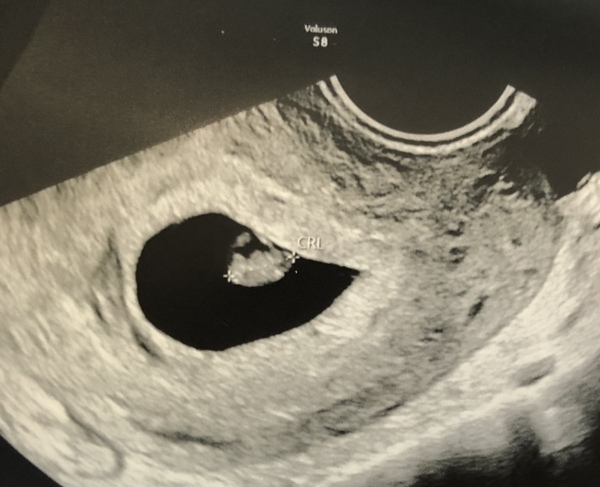

I had my viability scan today at 6+5 going by my dates, baby measured 6+4 which I’m happy with and had a strong heartbeat. Booked in for another one in 2.5 weeks, which I wasn’t expecting but is a nice surprise. They confirmed today that we’re eligible for the NIPT on the NHS too which is great news.

@ShootingStar94 mine measured 120bpm today at 6+4, my husband asked what range they’d expect and they said “at this point it should be over 100bpm, so 120bpm is really good.” - which means your 117bpm at 6+5 is perfectly fine! I hope this helps you relax a little.

@NoCallerID thank you so much, that is reassuring to hear. I was away from home for the previous scans and I intend to go and register with my doctor this week when I'm about 8 weeks and hope that he will do another ultrasound to show the heart rate has increased.